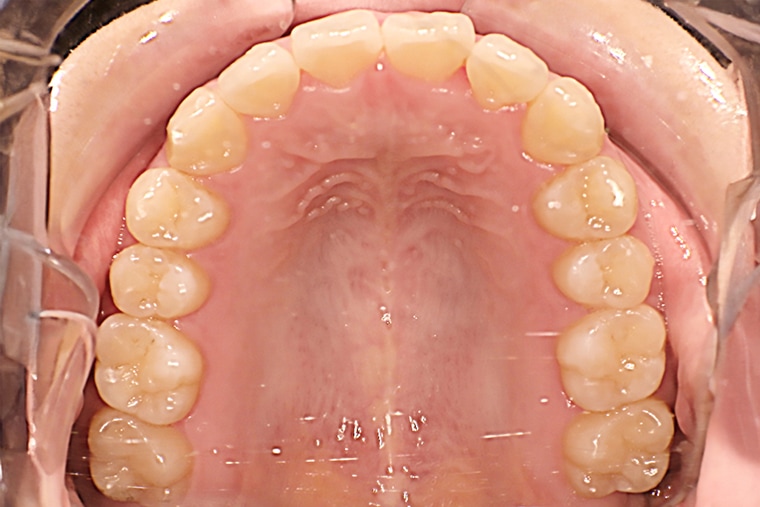

25歳男性ガタガタな歯のマウスピース矯正-矯正期間6ヶ月

- 治療費用

- 968,000円(税込)

- 治療期間

- 6ヶ月

- 性別

- 男性

- 年齢

- 25歳

- 抜歯

- 無し

- 治療方法

- マウスピース矯正(インビザラインModerate)による治療方法

- 治療リスク

- 1日22時間の装着時間を守らないと治療期間が遅くなり、歯並びの質が悪くなります

患者さまの声

歯の噛み合わせが一番気になっていたのでマウスピース矯正を始めました。

最初はちゃんと治るか不安でしたが、近所で一番大きい医院だったので安心できました。

約6ヶ月の治療で気になっていた部分はしっかり改善され、噛み合わせも良くなり満足しています。